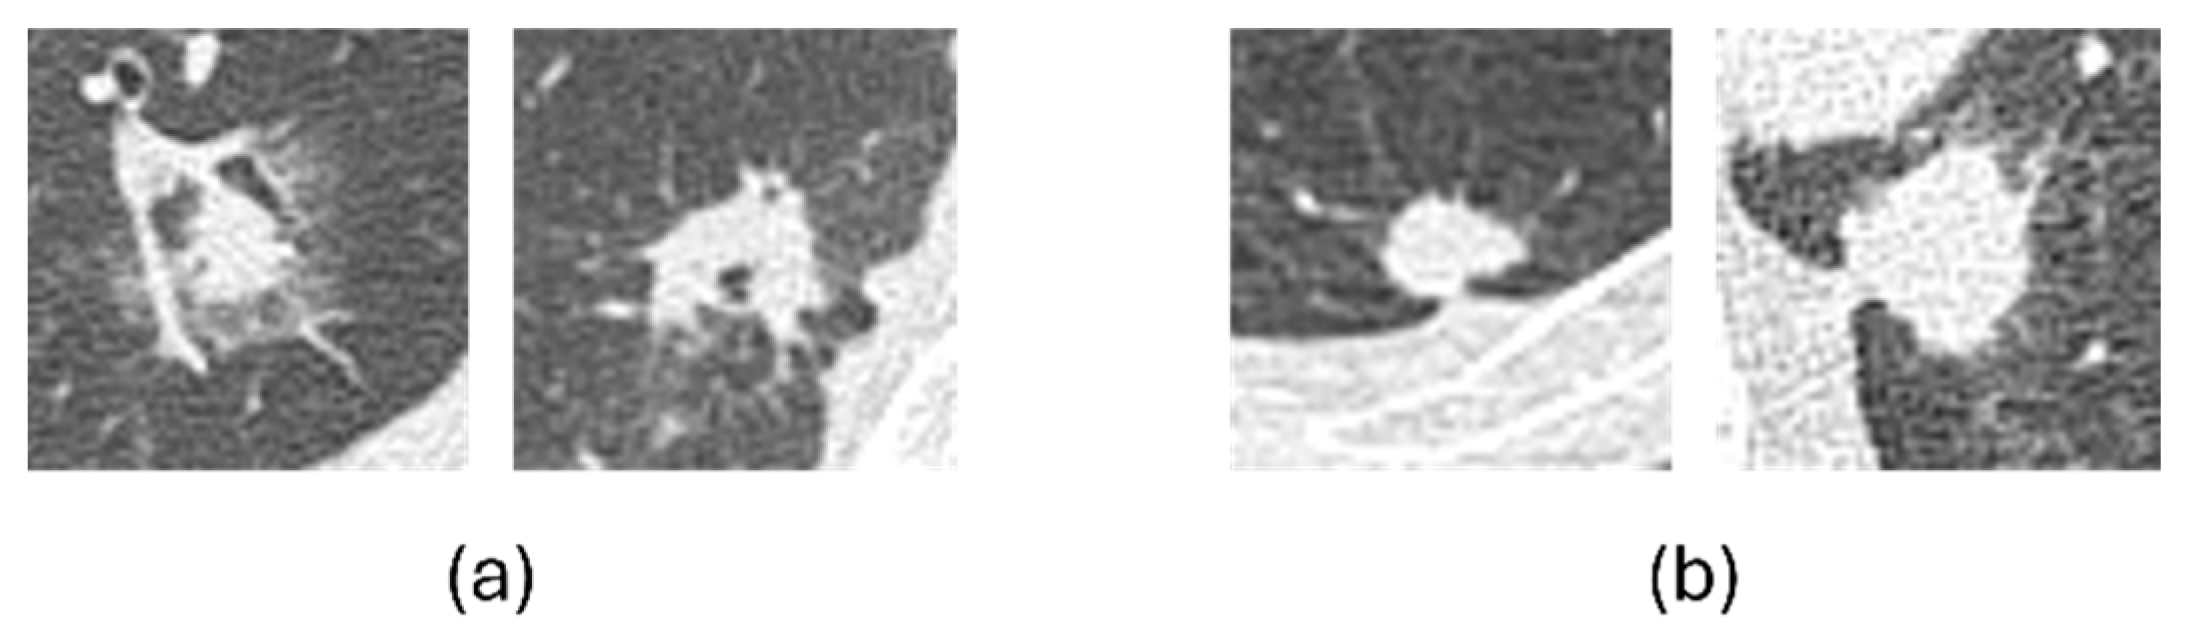

To further examine classification errors, Figure 8 shows representative examples of misclassified cases. In general, benign nodules that were misclassified as malignant tended to exhibit malignant-like characteristics, such as irregular shapes and indistinct margins, whereas malignant nodules misclassified as benign often appeared relatively round with well-defined borders. These patterns indicate that most errors were associated with overlapping visual characteristics between benign and malignant nodules.

Figure 8. Misclassified nodules. (a) Benign nodules as malignancy and (b) malignant nodules as benign.